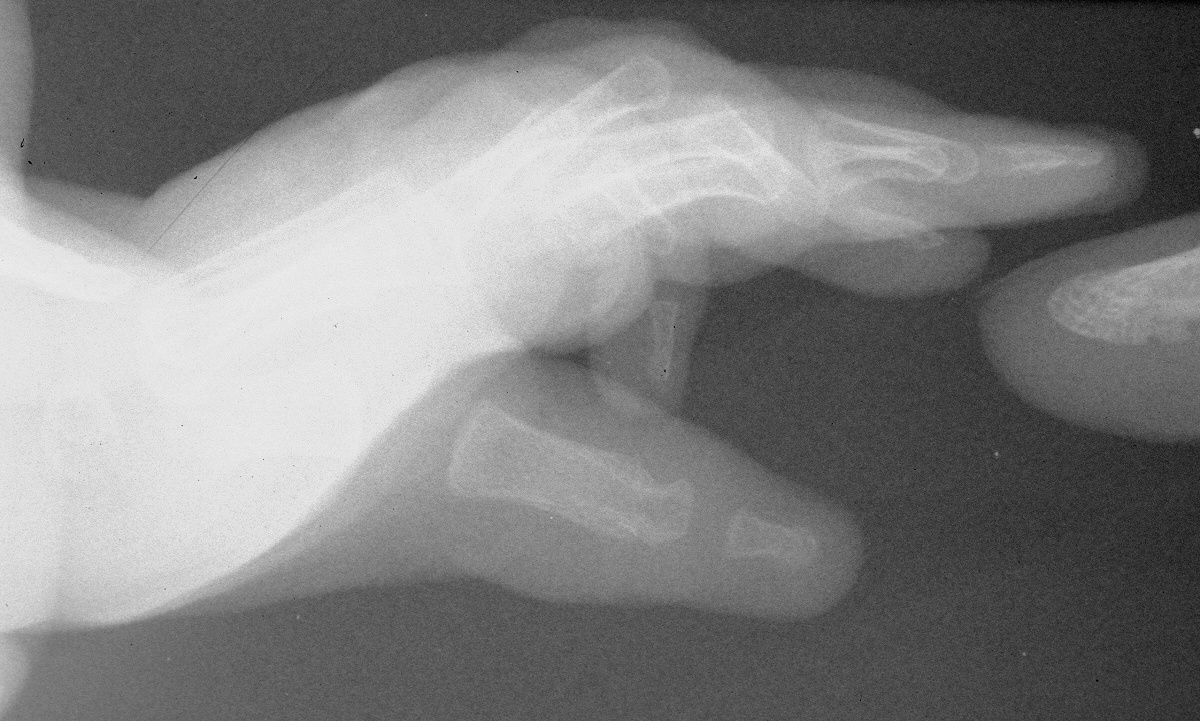

| This infant has

recovered from neonatal repairs of life threatening

cardiac defects, and is declared fit enough to "fix her

hands". This particular situation falls somewhere between the five fingered hand (absent true thenar development, adducted, not pronated) and a pure triphalangeal thumb. The middle phalanx is a delta phalanx, and could have been treated with excision, although there is disagreement in the literature about how well that procedure works. |

| Left hand: |

| Immediately preop. |